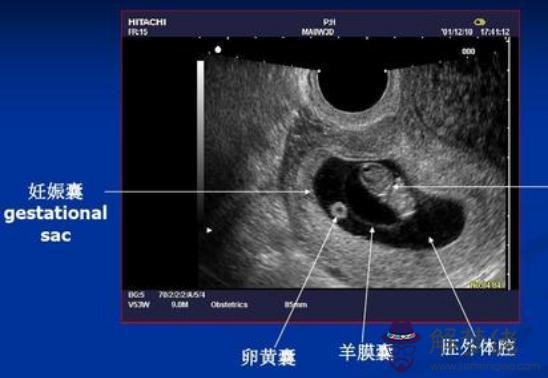

比如在 懷孕早期,根據孕囊的大小、胎芽的長度來判斷懷孕多少周了。

胎兒發育有規律,不同孕周的胎芽長度不同,檢查后,醫生只需要對應從表格里找胎芽對應的孕周就可以了。